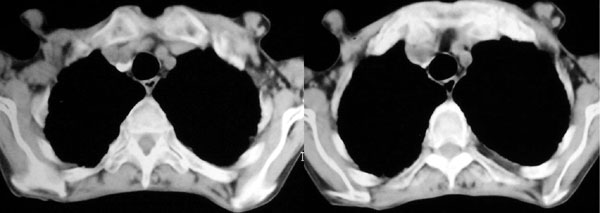

f 76 间断咳嗽 咳痰1年余 发热不明显 身体削瘦

征象:

1、右肺中叶近肺门区可见一空洞样病灶,内壁不规则,有与邻近支气管相通的征象,其外侧大片肺组织软组织状实变,余肺可见散在点、片絮状密度增高影,肺纹理可见明显增粗及串珠样改变;

2、纵隔气管前、隆突下、内乳组、心右前间隙以及右侧腋窝内均可见肿大的淋巴结节;

3、右侧胸膜增厚粘连,胸腔少量积液征像;

4、其它征像略。

诊断意见:

1、右侧中央型(空洞性)肺癌并双肺受累(包括转移、阻塞性炎症、癌性淋巴管炎);纵隔、右侧腋窝内淋巴结肿大、转移;右侧胸膜增厚粘连,胸腔少量积液;

2、双上肺陈旧性结核。

3、慢性支气管炎、肺气肿。